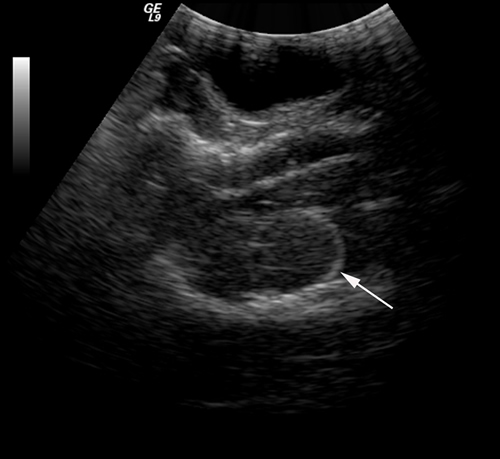

In this study, an epidural hematoma model was successfully established (Figure 1). The MAP of the experimental dogs was at 88.7 ± 14.3 mmHg before trauma (the volume of sacculus was 0ml) and the MAP was 98.2±8.1 mmHg (the volume of sacculus was around 9ml) before the CPP reached nearly 0 mmHg. A linear relationship between CPP and ICP was found and described by the equation CPP = MAP-ICP. Other vital signs of the experimental dogs were generally stable.

Figure 1: An epidural hematoma model was established, and the position of sacculus was confirmed via ultrasound (white arrow).